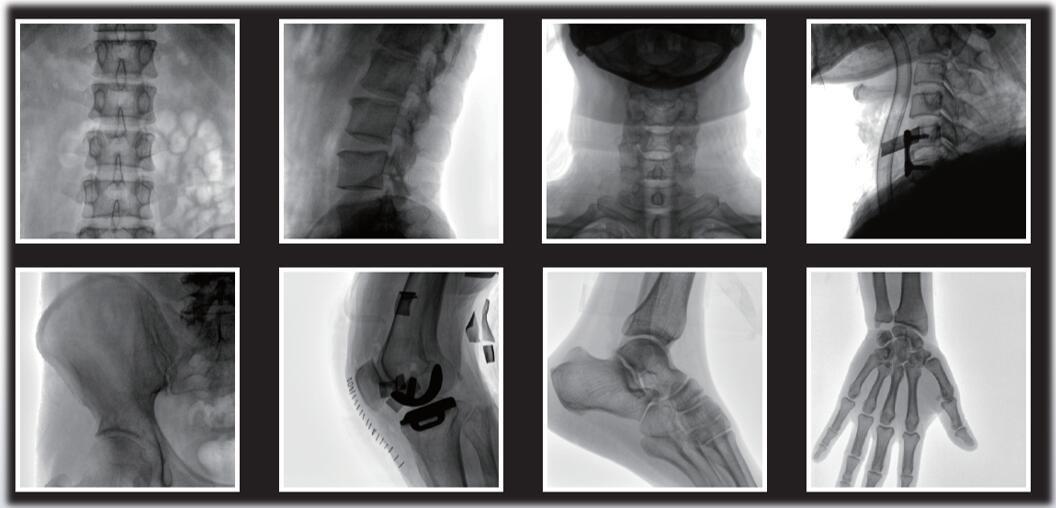

大尺寸动态平板探测器,图像清晰细腻,满足临床多种检查。

采用了多分辨率图像增强处理技术,不同部位不同图像处理。

平板小C臂在骨科手术中的定位、诊断、微创手术的开展与治疗中发挥独特的作用。作为一名医生,您需要清晰的图像质量来帮助您应对更具挑战性的介入治疗。PLX118系列平板小C臂为您提供优良的图像、灵活的操作体验和更低的剂量表现。如果您想采购,或了解产品具体参数,欢迎咨询400-025-6366。